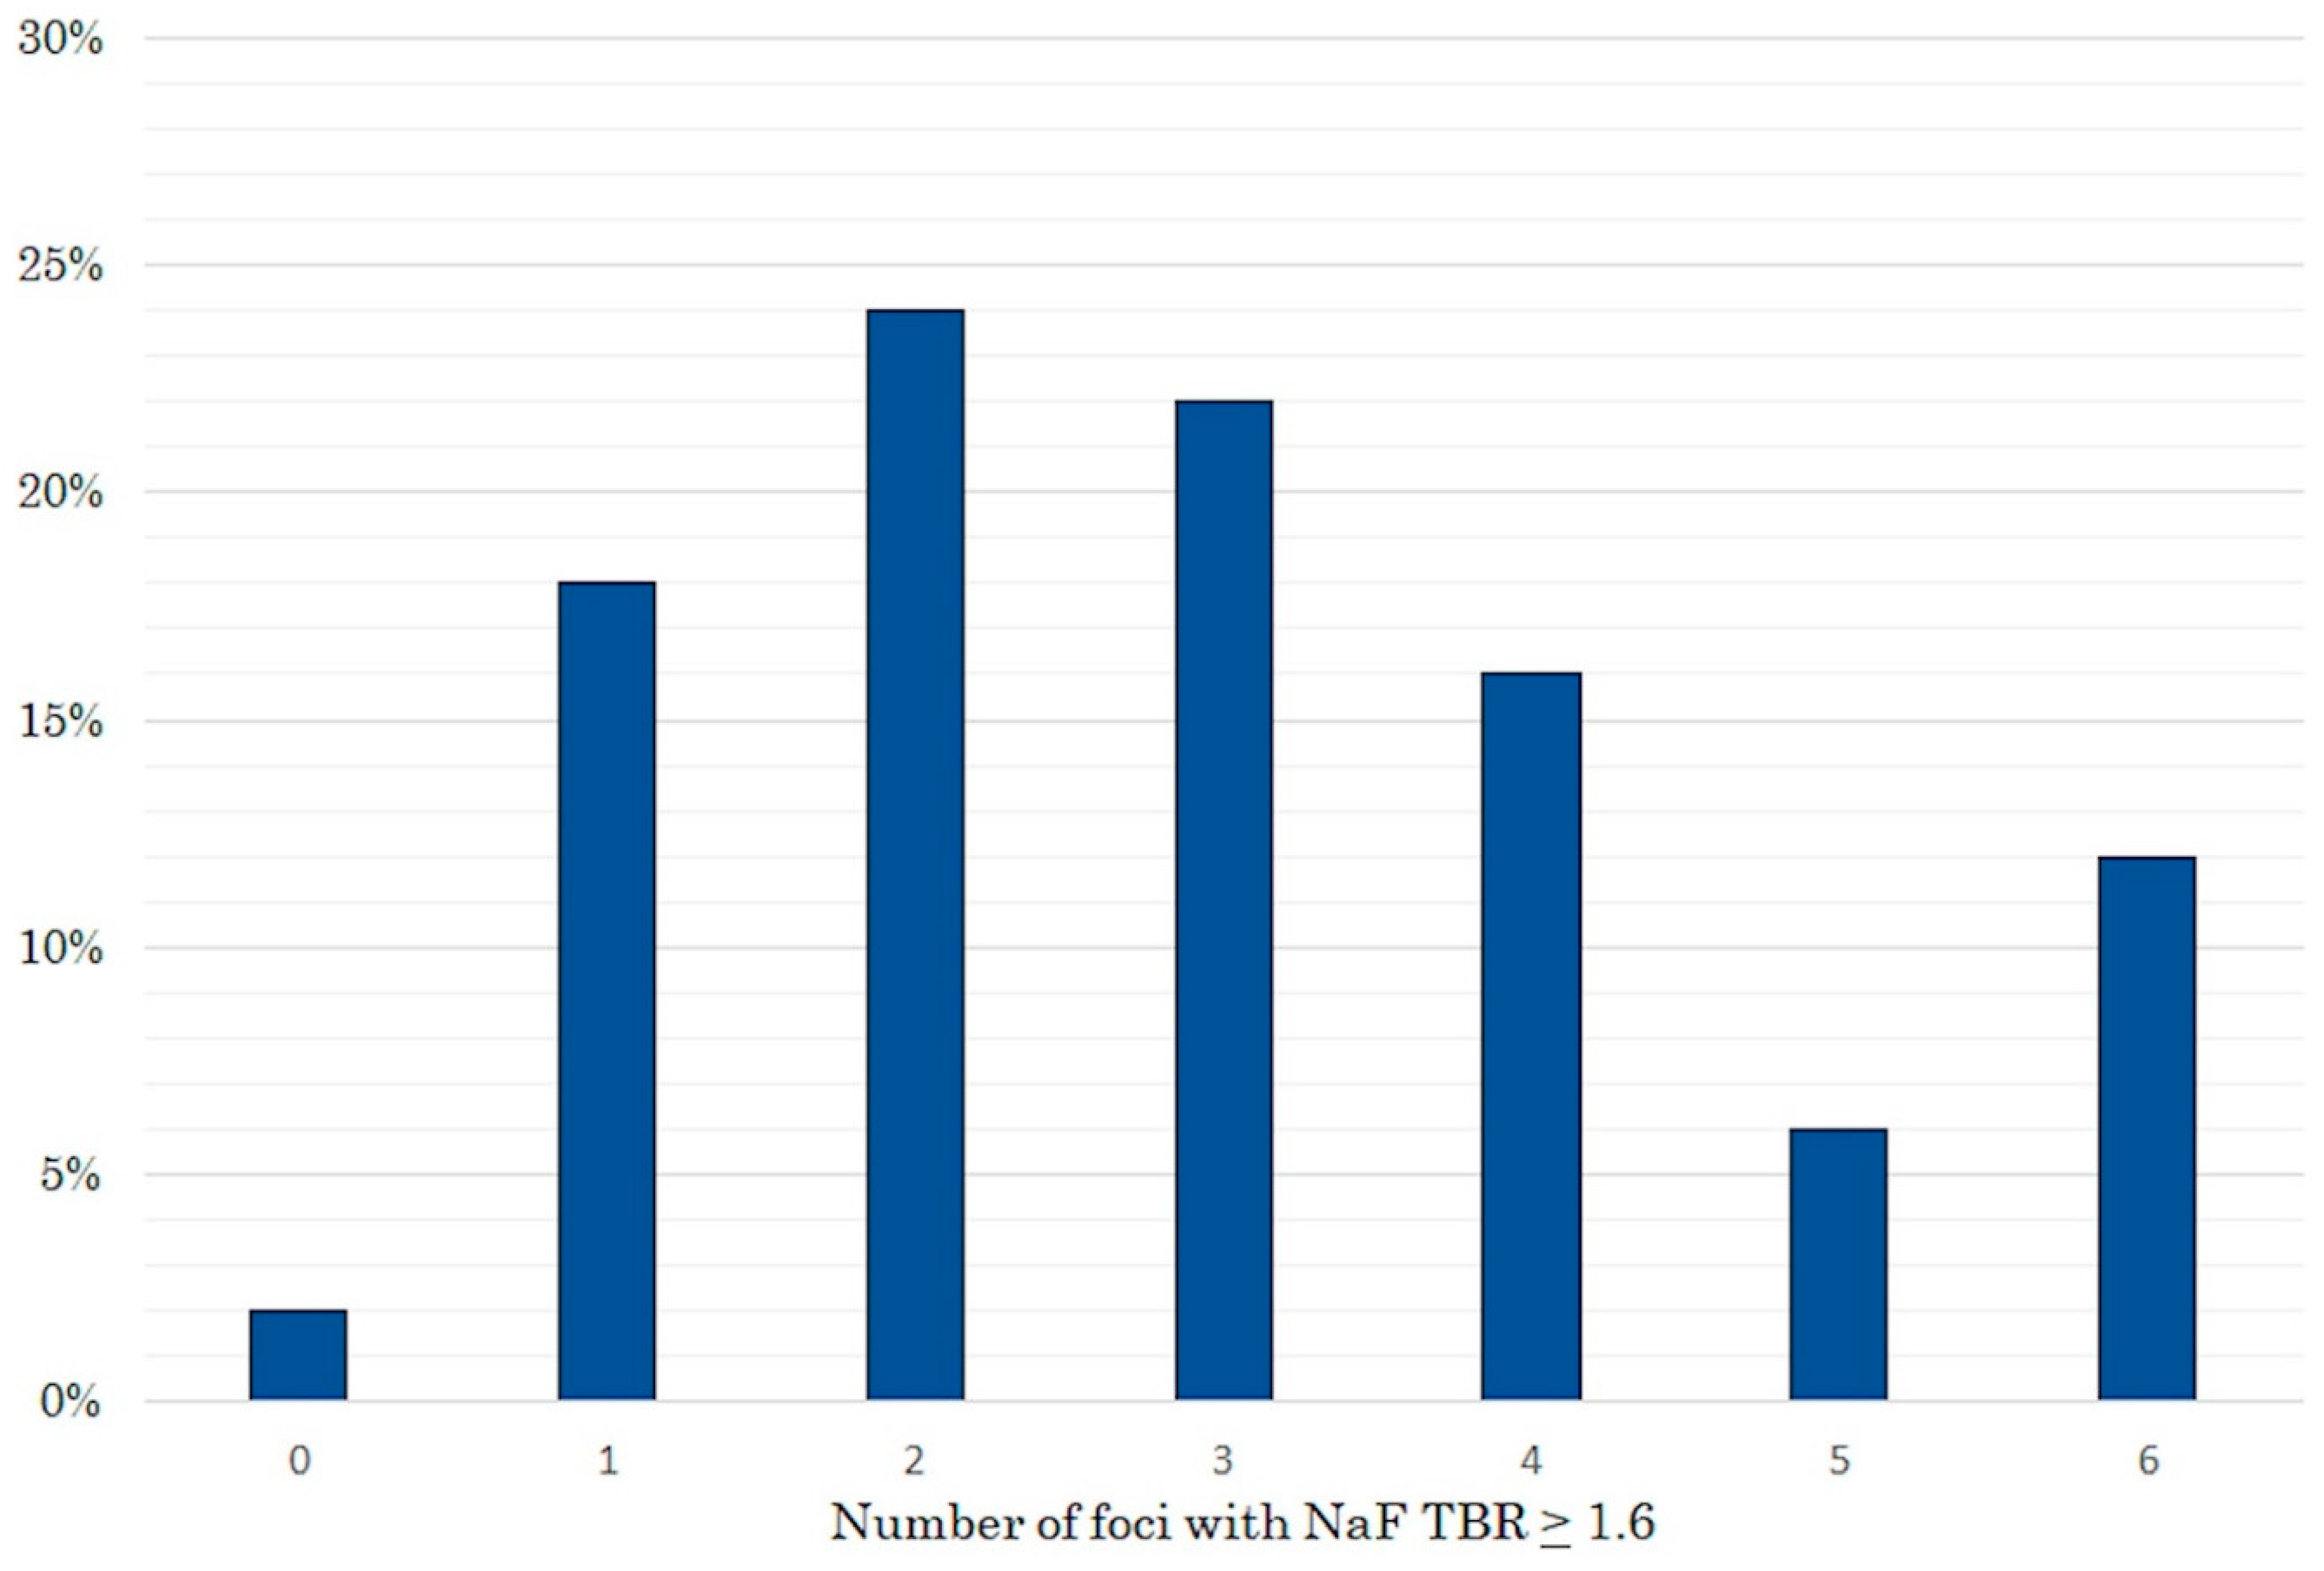

2. Results

4.3.2. Positron Emission Tomography with 18F-Sodium-Fluoride

4.3.3. Image Analysis